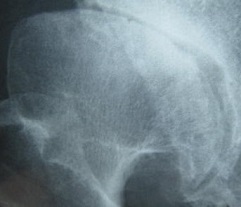

昨年か一昨年の股関節の写真です

骨の欠け 骨どうしが一部接触 骨の壊疽 臼蓋不全で骨の掛かりが浅い・・・

前からの写真ですが後ろからのは怖くて見られません

大腿骨頭の変形、坐骨の損傷、臼蓋不全 関節の軋轢音